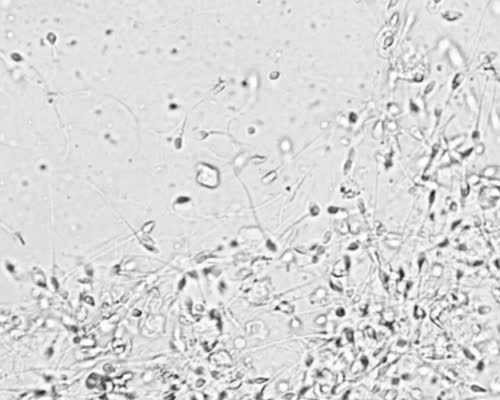

术前检查是供(借)卵试管婴儿必不可少的项目,包括血型、血常规、肝肾功能、乙肝丙肝检查、精液培养、阴道分泌物培养、双侧梅毒筛查、艾滋病筛查、染色体检查等,主要目的是让医生了解患者的病情,制定治疗方法。